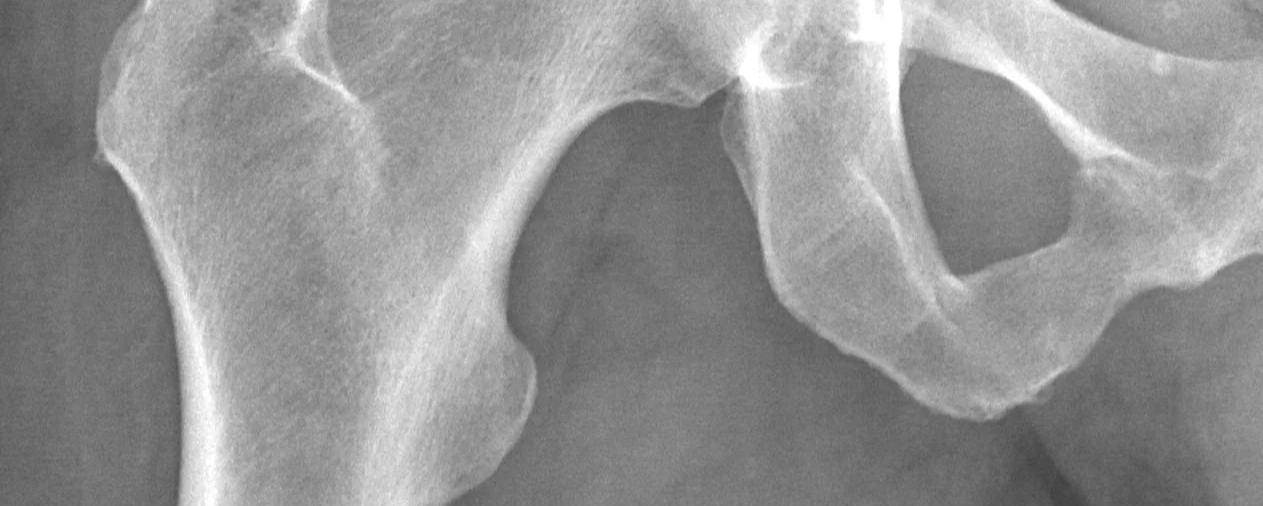

Bone fractures become increasingly serious as we age. Across her lifetime, a woman has a 50% risk of fracturing a bone due to osteoporosis. If she fractures her hip, her chance of death without surgery in the following 12 months. With surgery, that risk of death is still 29% after a hip fracture.

Other symptoms are stooping, posture changes, and back pain. Bone fractures are not just painful and debilitating, they can be life-threatening, especially fractures in the hip and spine.